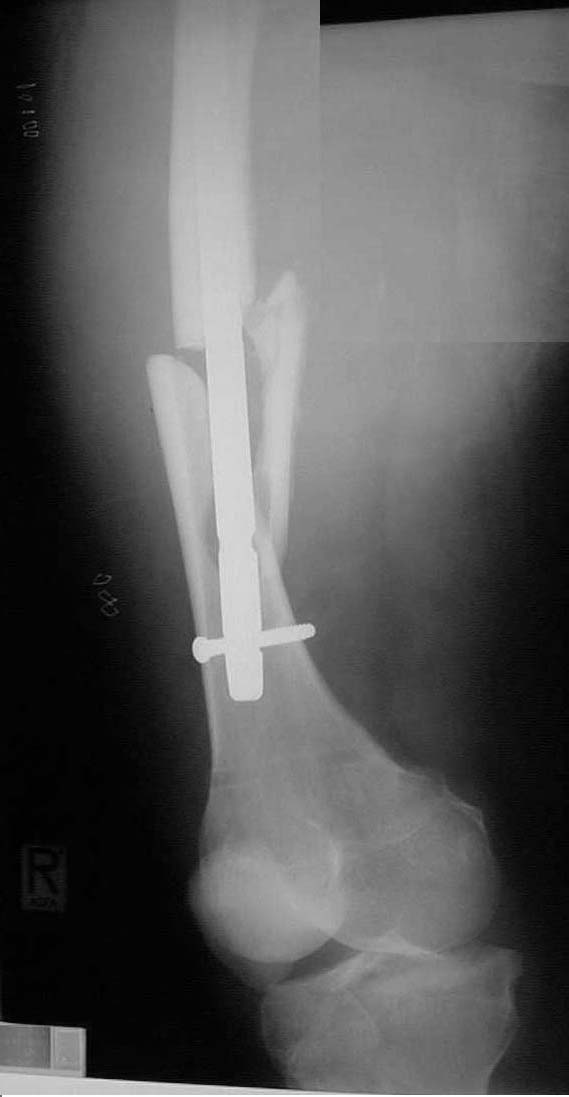

Attached here few x-rays of a multi-trauma patient. He is a 51years old man,sustain MVA at 08/15/99 and refer to our hospital few days ago, more than twoweeks after injury. He sustain Bilateral femoral fracture including femoralneck, A right humerus fracture, right distal radius fx, left open ulnar fx,right tibial plateau (type III) fx and Chopart fracture dislocation of the rightfoot. At the other hospital where he was admitted, He underwent laparotomy andfixation of both femur by reconstruction IMN, application of Ex Fix to thehumerus, and reduction and K.W. fixation of the Rt foot. He is currently stable and conscious. He is scheduled next week for replacing of the Rt IMN to aretrograde nail and pinning (6.5 mm screws) of the neck fracture, fixation ofthe ulna, distal radius and tibial plateau.

AP Pelvis

Lt femur

Rt femur

We decided to fix the Lt femur with a few lag screws on the proximal part andstabilize the femur with long Richard plate that was inserted in a sub-muscularfashion, in order to avoid opening the main shaft fx (the so-called biologicfixation - see Lt leg incisions.).

On the Rt side I replaced the recon nail with a longer one (accepting its toolateral and anterior entering point), I added a proximal locking screw (anterior toposterior) in the subtrochanteric region through a self-made extra hole, and two 6.5cancellous hip screws posterior to the nail.